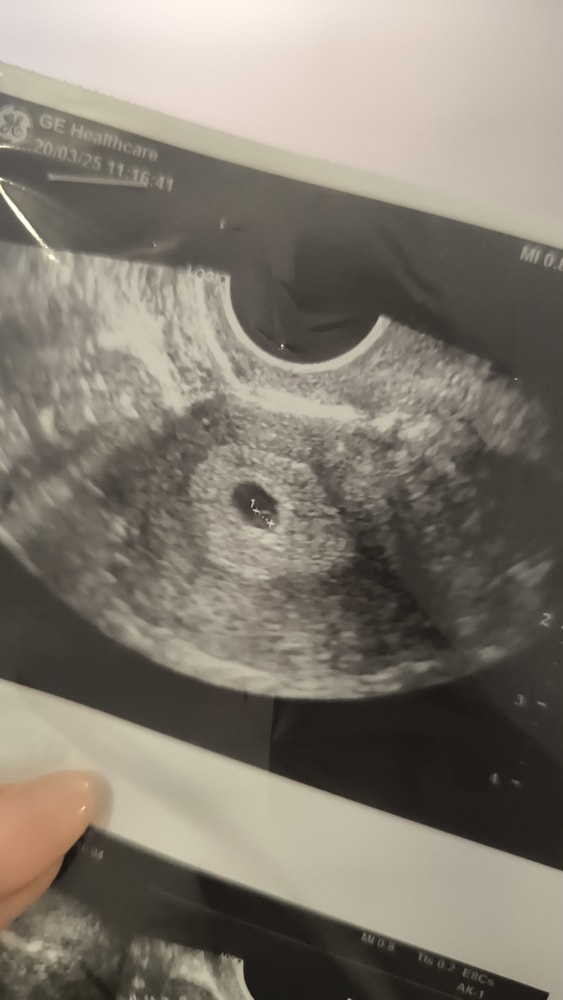

УЗИ, КТГ, доплер25.03 была на УЗИ (были коричневые выделения) - жм 2,6 см

Сегодня (27.03) была на плановом приёме у своего врача - она на УЗИ жм не увидела.

Вот прошлое УЗИ.